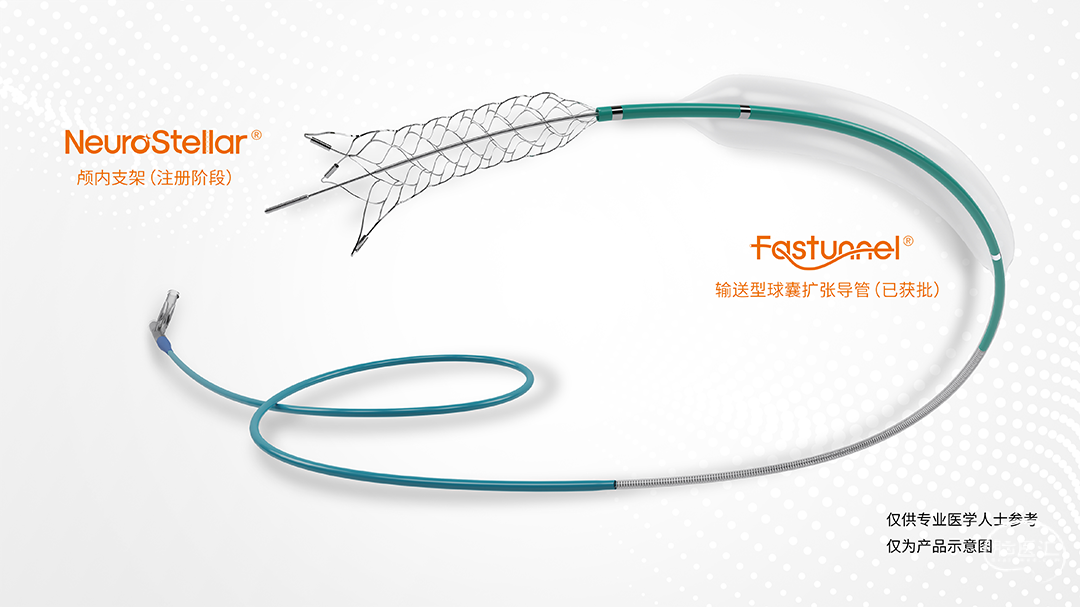

术中涉及介入器械选择

加奇生物 21系列 Fastunnel®输送型球囊扩张导管 2.0*10mm

自膨式闭环支架 4*16mm

21系列 Fastunnel®输送型球囊扩张导管 2.0*10mm用10atm压力缓慢预扩张M1远端。

21系列 Fastunnel®输送型球囊扩张导管 2.0*10mm用12atm压力缓慢预扩张M1近端。

经21系列 Fastunnel®输送型球囊扩张导管释放自膨式闭环支架 4*16mm。

1、对于颅内动脉狭窄的球囊扩张和支架置入治疗,传统手术需要球囊导管和支架微导管两种器材进行同轴交换,过程中无论射线量还是微导丝的前后移动均会增大患者的手术风险。而使用Fastunnel®输送型球囊扩张导管,可以避免上述的反复交换操作,特别是在相对平直的血管条件下,可以有效减轻术中的风险,缩短手术时间,提高了手术安全性,具有较好的应用前景。

2、该病例狭窄段长度较长,手术中使用Fastunnel®输送型球囊扩张导管 2.0×10mm,分别采用10atm和12atm由远及近对左侧大脑中动脉狭窄部位进行扩张,后续释放自膨式闭环支架过程中注意系统张力的调整。

3、Fastunnel®输送型球囊扩张导管采用同轴结构设计,充盈腔相比普通快交球囊更小,在体外应做到充分排气,以免影响术中观察狭窄扩张效果。